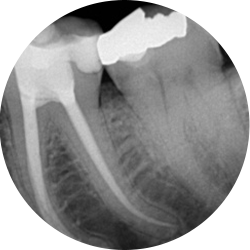

My old root filling is failing, can I get it redone?

Yes sometimes endodontic treatments are not successful for a multitude of reasons and have to be redone.

A careful assessment will be made of your tooth to see if retreatment is the best option for you. Sometimes teeth have other more significant problems that may have a significant impact on the success of the retreatment and in these cases the tooth may have to be removed.